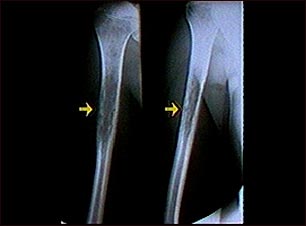

Rayos X de un sarcoma de Ewing

Esta radiografía muestra un tumor óseo maligno (sarcoma de Ewing) del hueso del brazo (húmero). Este tipo de tumor generalmente aparece durante la niñez o la adolescencia.